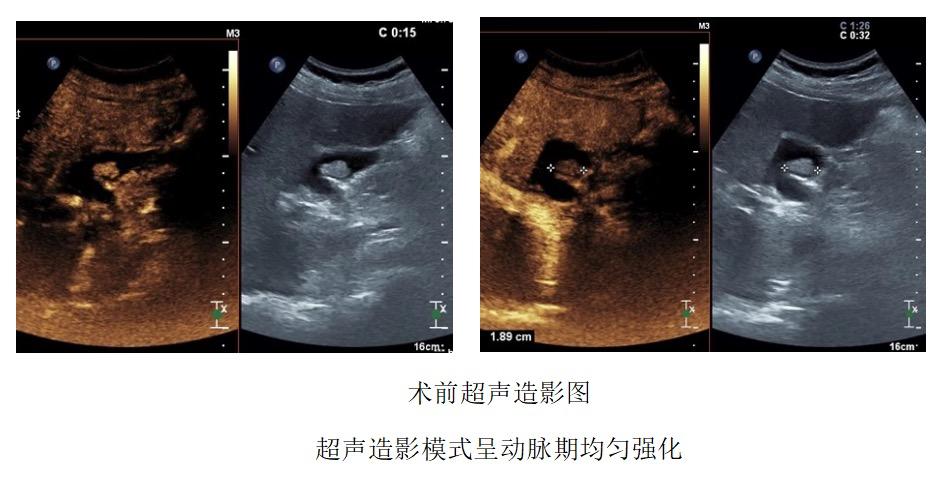

因胆囊占位>10mm,生长速度略快,腺瘤性息肉可能性大,与患者及家属沟通后,决定打破传统外科切除治疗方式,拟定“超声引导下胆囊占位穿刺活检术+射频消融术”同时进行。

术中即刻造影:可见占位部分强化,仍具有活性,未消融完全。

进行“修补”巩固,再次启动消融,使占位彻底“灭活”。

再次造影可见占位呈动脉期“无强化”,消融完成。